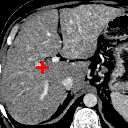

Figure 7: Example comparison among ADDD + inv (c/d), ADDD (e/f), ADD (g/h), AD (i/j) and D (k/l) networks.

In Figure 7, we compare ADDD + inv, ADDD, ADD, AD and D. It shows that network cascading better aligns the images with the presence of large displacement, while the invertibility loss has a remarkable effect on the liver boundary.